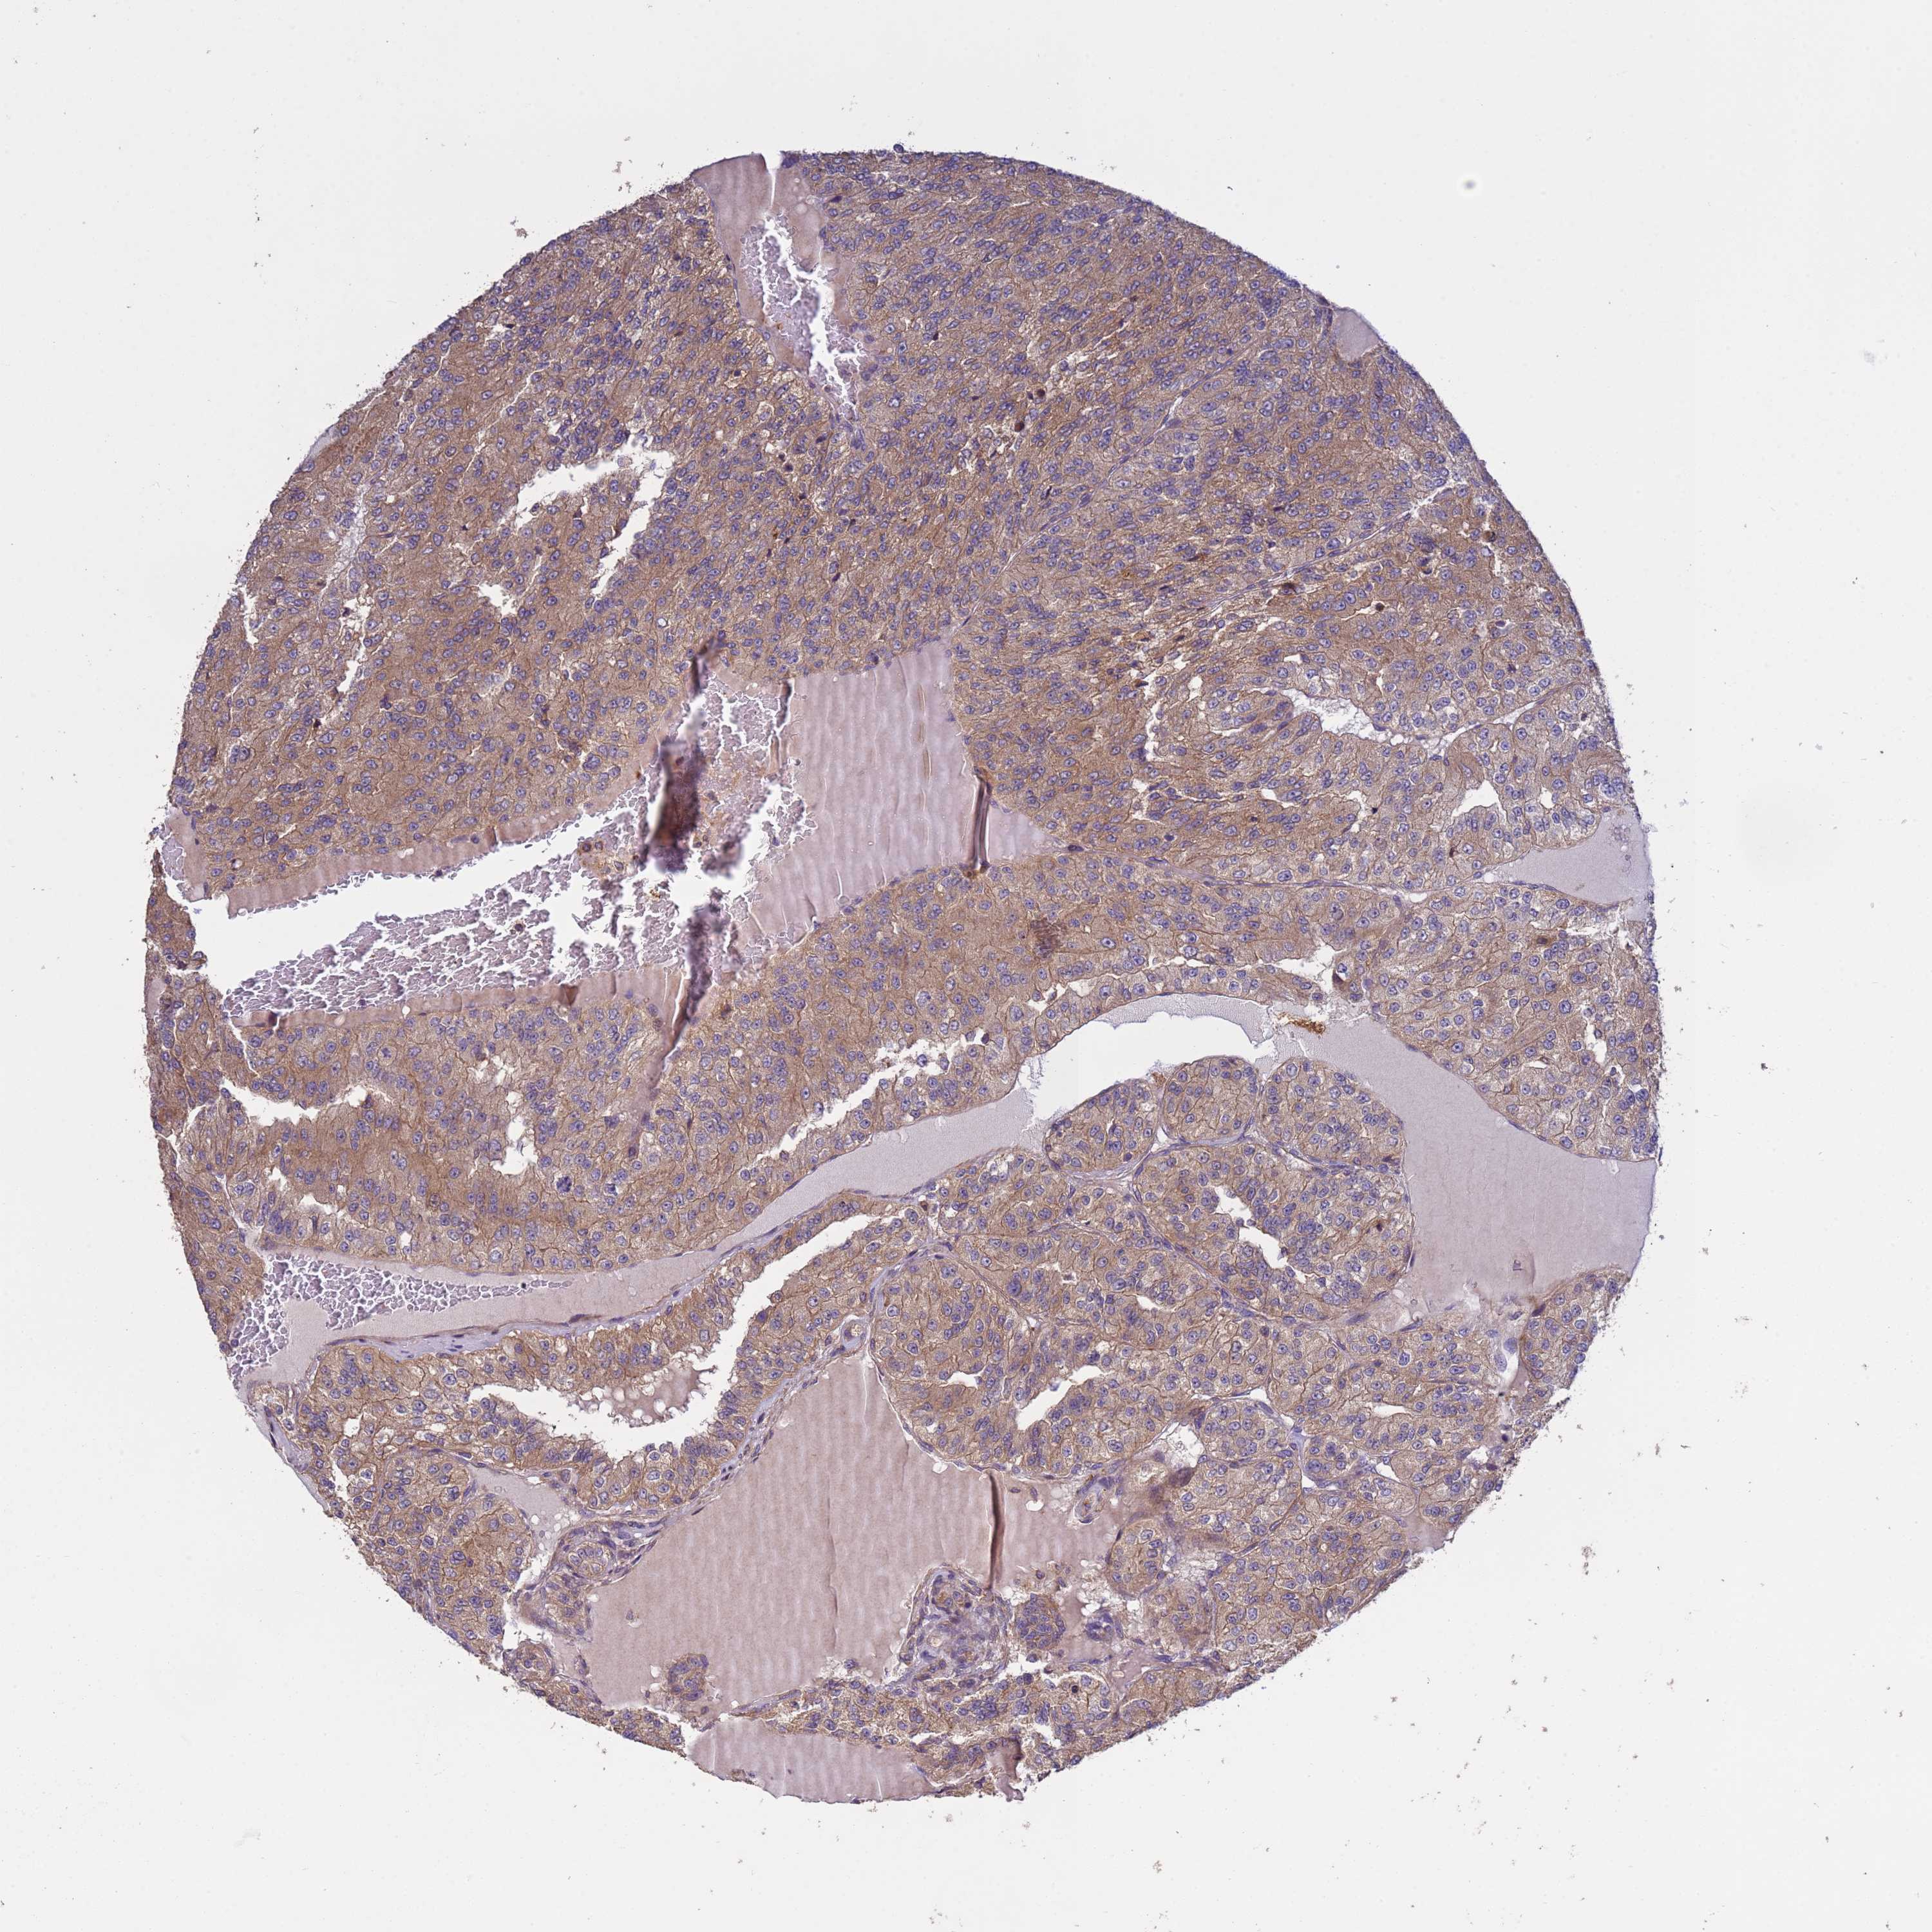

KIDNEY RENAL CLEAR CELL CARCINOMA (VALIDATION) - Interactive survival scatter ploti

The Survival Scatter plot shows the clinical status (i.e. dead or alive) for all individuals in the patient cohort, based on the same data that underlies the corresponding Kaplan-Meier plots. Patients that are alive at last time for follow-up are shown in blue and patients who have died during the study are shown in red.

The x-axis shows the expression levels (FPKM) of the investigated gene in the tumor tissue at the time of diagnosis. The y-axis shows the follow-up time after diagnosis (years). Both axes are complimented with kernel density curves demonstrating the data density over the axes. The top density plot shows the expression levels (FPKM) distribution among dead (red) and alive patients (blue). The right density plot shows the data density of the survived years of dead patients with high and low expression levels respectively, stratified using the cutoff indicated by the vertical dashed line through the Survival Scatter plot. This cutoff is automatically defined based on the FPKM cutoff that minimizes the p-score. The cutoff can be changed by dragging the vertical line or by entering a cutoff value in the square labeled "Current cut-off".

Under the Survival Scatter plot the p-score landscape (black curve; left axis) is shown together with dead median separation (red curve; right axis). Dead median separation is the difference in median mRNA expression between patients who have died with high and low expression, respectively. It is calculated as follows: median FPKM expression of dead patients with high expression - median FPKM expression of dead patients with low expression. This is intended to aid the user in visually exploring custom cutoffs and the associated p-scores and dead median separation.

Individual patient data is displayed and can be filtered by clicking on one or more of the category buttons on the top of the page. Categories describing expression level and patient information include: high, low, alive, dead, female, male and tumor stages. The scale of the x-axis can be toggled between linear and log-scale by clicking on the "x log" button. Mouse-over function shows TCGA ID, patient information and mRNA expression (FPKM) for each patient.

& Survival analysisi

Kaplan-Meier plots summarize results from analysis of correlation between mRNA expression level and patient survival. Patients were divided based on level of expression into one of the two groups "low" (under cut off) or "high" (over cut off). X-axis shows time for survival (years) and y-axis shows the probability of survival, where 1.0 corresponds to 100 percent.

RAB10 is not prognostic in Kidney Renal Clear Cell Carcinoma (validation)

Best expression cut offi

Based on the FPKM value of each gene, patients were classified into two groups and association between prognosis (survival) and gene expression (FPKM) was examined. The best expression cut-off refers the FPKM value that yields maximal difference with regard to survival between the two groups at the lowest log-rank P-value. Best expression cut-off was selected based on survival analysis .

When clicking on this number, the vertical dashed line indicating cut-off, the interactive survival plot, and the Kaplan-Meier curve will be adjusted to show results based on the best expression cut-off.

: 95.16

P scorei

Log-rank P value for Kaplan-Meier plot showing results from analysis of correlation between mRNA expression level and patient survival.

N/A

TCGA RNA samplesi

RNA-seq data is reported as average FPKM (number Fragments Per Kilobase of exon per Million reads), generated by the The Cancer Genome Atlas (TCGA) .

Normal distribution across the dataset is visualized with box plots, shown as median and 25th and 75th percentiles. Points are displayed as outliers if they are above or below 1.5 times the interquartile range. FPKM values of the individual samples are presented next to the box plot.

Average pTPM 81.4

Number of samples 100